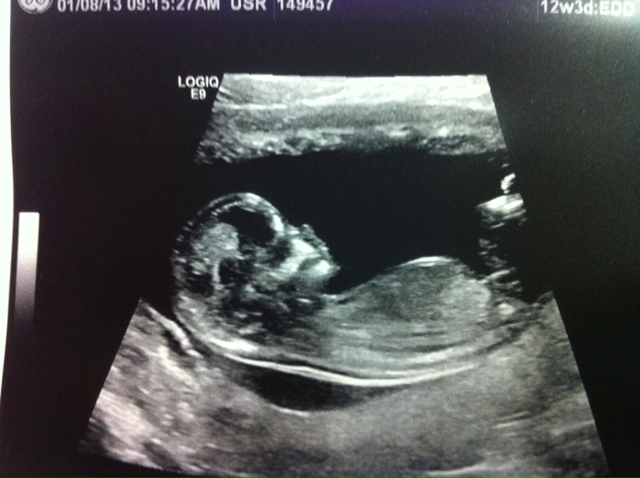

As you can see, the profile shot on my 12w 3d u/s is very clear. No so sure about the nub. In fact, I'm not really sure WHICH is the nub? Guesses? Clarification? Thanks so much!